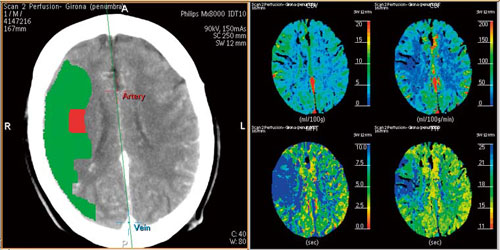

Advanced Brain Perfusionには,“Summary Map”表示機能が標準装備されている。CBF,CBV,およびMTTから梗塞領域と境界領域(ペナンブラ)を想定し,頭部アキシャル断面像上にカラー表示を行う。従来のCBF,CBV,MTTの画像とともに参照することにより,より迅速な診断の手助けになるものと考えている(図3)。

図3 Summary Map |